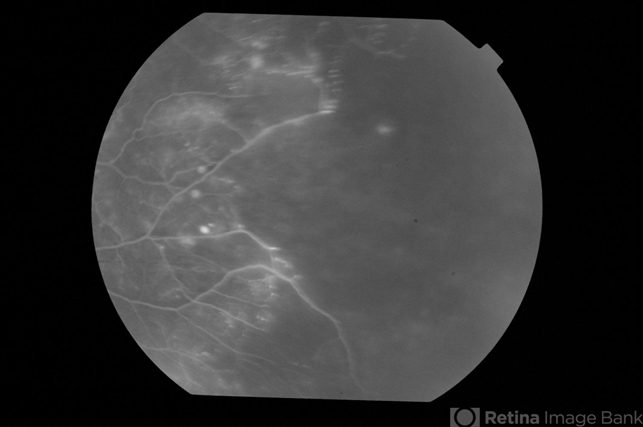

- Adult Coats Disease

- Left fundus of a 61-year-old non diabetic, non hypertensive lady complaining of vision deterioration for 1 year showed massive hard exudates at the macula. Fluorescein angiography revealed microvascular abnormalities over the posterior pole and temporal midperiphery and extensive capillary non-perfusion over the temporal retinal quadrants. OCT revealed macular edema. Fellow eye fundus and angiogram were normal.